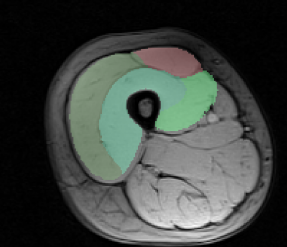

Dataset. The dataset consists of 30 MRI volumes of the thigh region of dimensions . The various segments correspond to 4 different muscle groups together with the background class. We randomly split the dataset into 80% for training and 20% for testing. In order to reduce the training time for both our method and the baselines, we divide each volume into volumes of dimension .

Results. Fig. 1 shows the test loss for three different methods: (i) the initial hand-tuned parameters ; (ii) the baseline structured SVM with distance transforms; and (iii) our proposed approach using latent SVM. As can be seen from Fig. 1, latent SVM provides significantly better results than the baselines—even when using the distance transform. For the 4 x 5 hyperparameter settings that we report (that is, four different values of and 5 different values of ), latent SVM is significantly better than SVM in 15 cases, and significantly worse in only 2 cases. Note that latent SVM provides the best results for very small values of , which indicates that the upper bound on the empirical risk in tight. As expected, for sufficiently large values of , all the methods provide similar results. For the best settings of the corresponding hyperparameters, the percentage of incorrectly labeled voxels as follows: (i) for , ; (ii) for structured SVM, ; and (iii) for latent SVM, . Fig. 2 shows some example segmentations for the various methods.